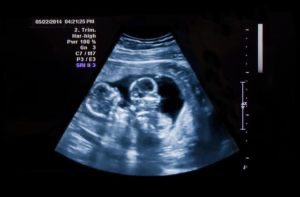

Pregnant with twins!

Pregnant with twins

Simone and her partner had been trying to have a baby for 2 years. Following recurrent miscarriage her doctor ordered blood tests which diagnosed Anti-Phospholipid Syndrome (APS). Just days later, they were advised they were 7 weeks pregnant with twins.